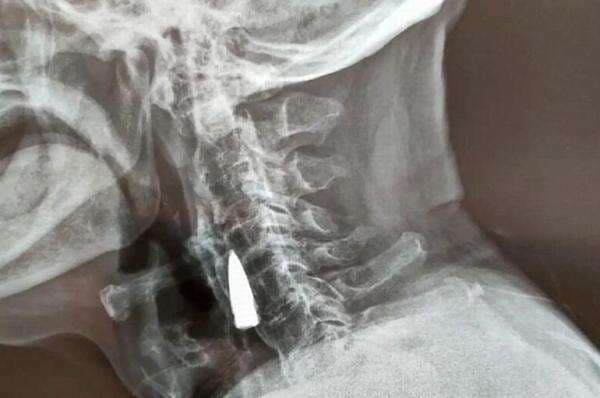

Gile 77 Tahun Peluru Bersarang Di Leher

Sebuah peluru bersarang di leher seorang veteran perang selama 77 tahun. Peluru itu baru terungkap setelah tim dokter melakukan rontgen terhadap veteran perang tersebut.

Namun, dia sama sekali tak sadar ada peluru yang bersarang di lehernya. Untungnya, amunisi yang bersarang itu tidak berbahaya bagi kesehatannya.

Karenanya, kendati dia telah memeriksakan diri ke rumah sakit di Kota Shandong, China, tim dokter tidak mengangkat peluru tersebut. Karena, jika diangkat, risikonya malah besar, mengingat usianya sudah sepuh.